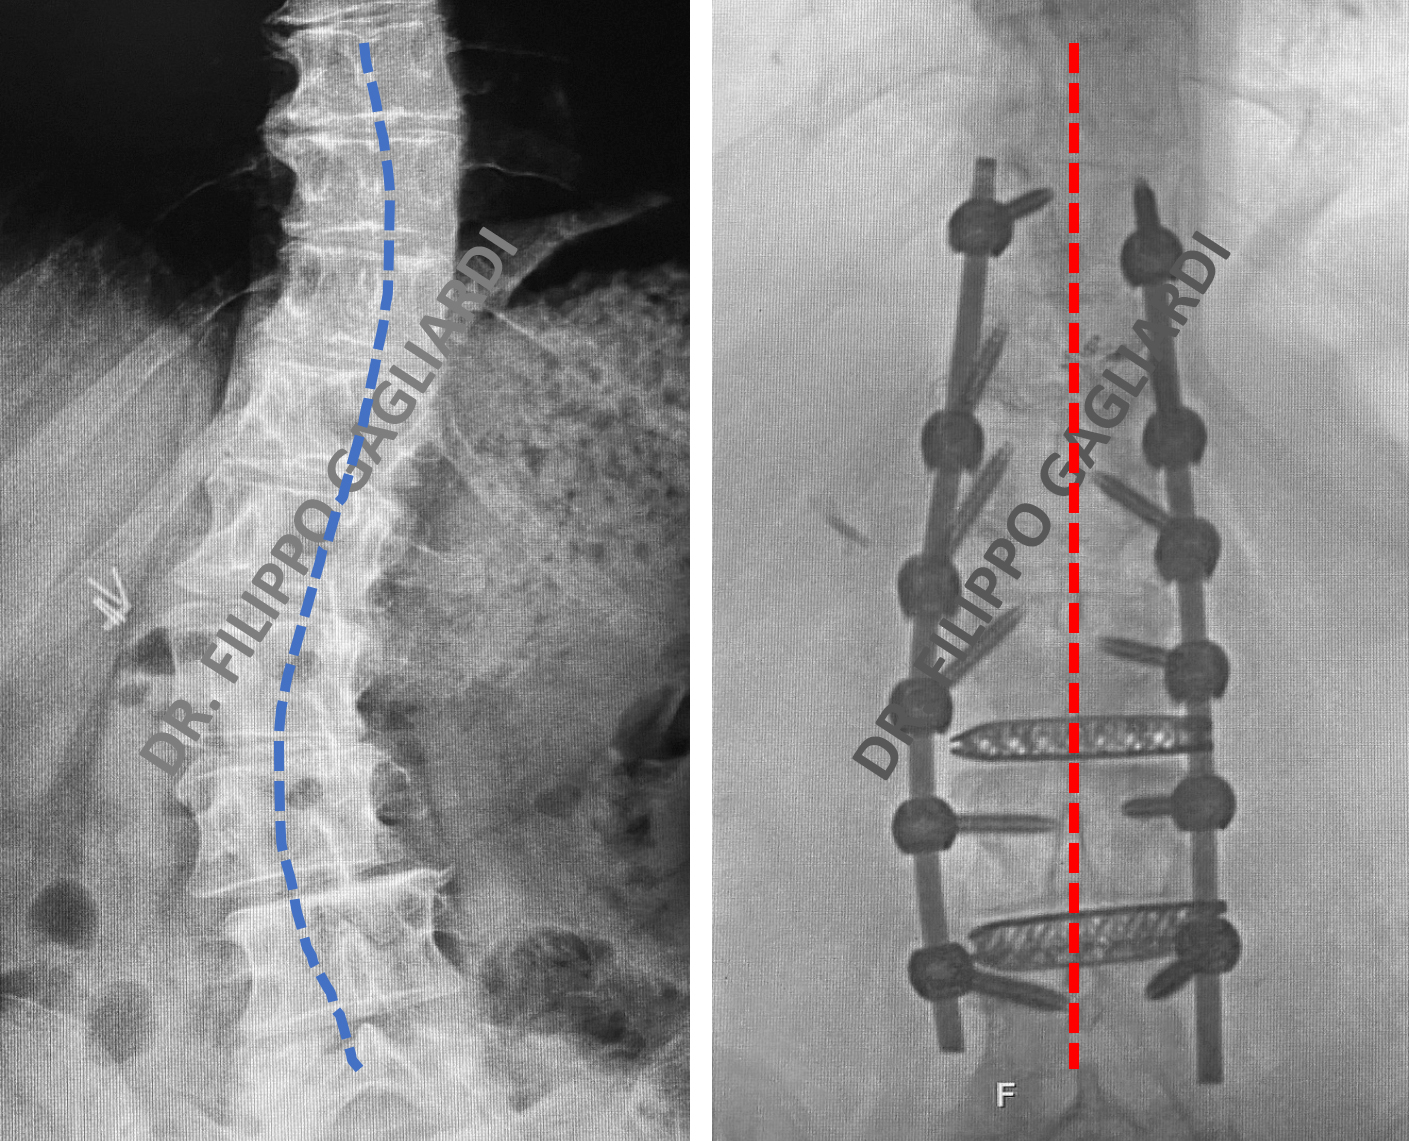

Caso di un grave scoliosi degenerativa

SI tratta di una donna di 50 anni. Il dolore, ormai resistente alle terapie mediche e conservative, provoca una severa limitazione della sua vita quotidiana e di relazione. La paziente è stata trattata con successo dal neurochirurgo, il Dr. Filippo Gagliardi. Come si vede sulla lastra di controllo si può osservare un ripristino completo del riallineamento coronale. Questo é ottenuto mediante una tecnica combinata XLIF e artrodesi posteriore mini-invasiva. La paziente è tornata ad una qualità di vita normale. Si evidenzia la completa regressione della sintomatologia dolorosa ed una ottima performance funzionale.

Riallineamento coronale.